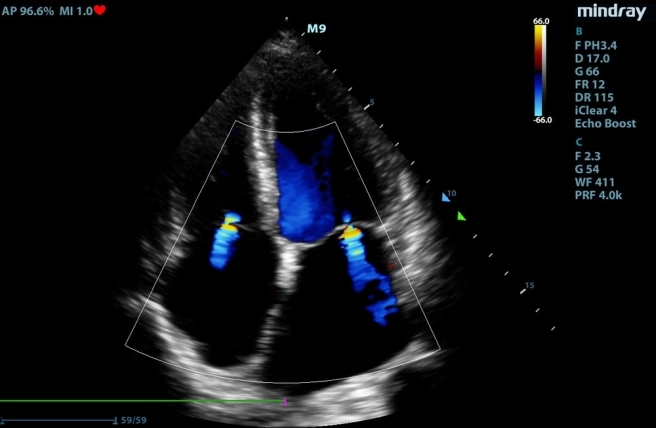

Konsultacja kardiologiczna przed znieczuleniem jest konieczna by ocenic ryzyko anestezji. Można ją wykonać wszystkim pacjentom, ale szczególnie zaleca się ją zwierzętom starszym, chorym oraz ras predysponowanych do schorzeń kardiologicznych (CKCS, dobermany, koty brytyjskie, Maincoon, psy ras małych).

W przypadku chorób serca nabytych lub wrodzonych, możliwość komplikacji podczas zabiegu znacząco rośnie, dlatego wcześniejsza ocena morfologii i funkcji serca jest tak ważna, by ograniczyć ryzyko tych powikłań. W przypadku pacjentów chorych kardiologicznie, wcześniejsze wprowadzenie odpowiednich leków minimalizuje powikłania i umożliwia sedację oraz dalszą diagnostykę obrazową.